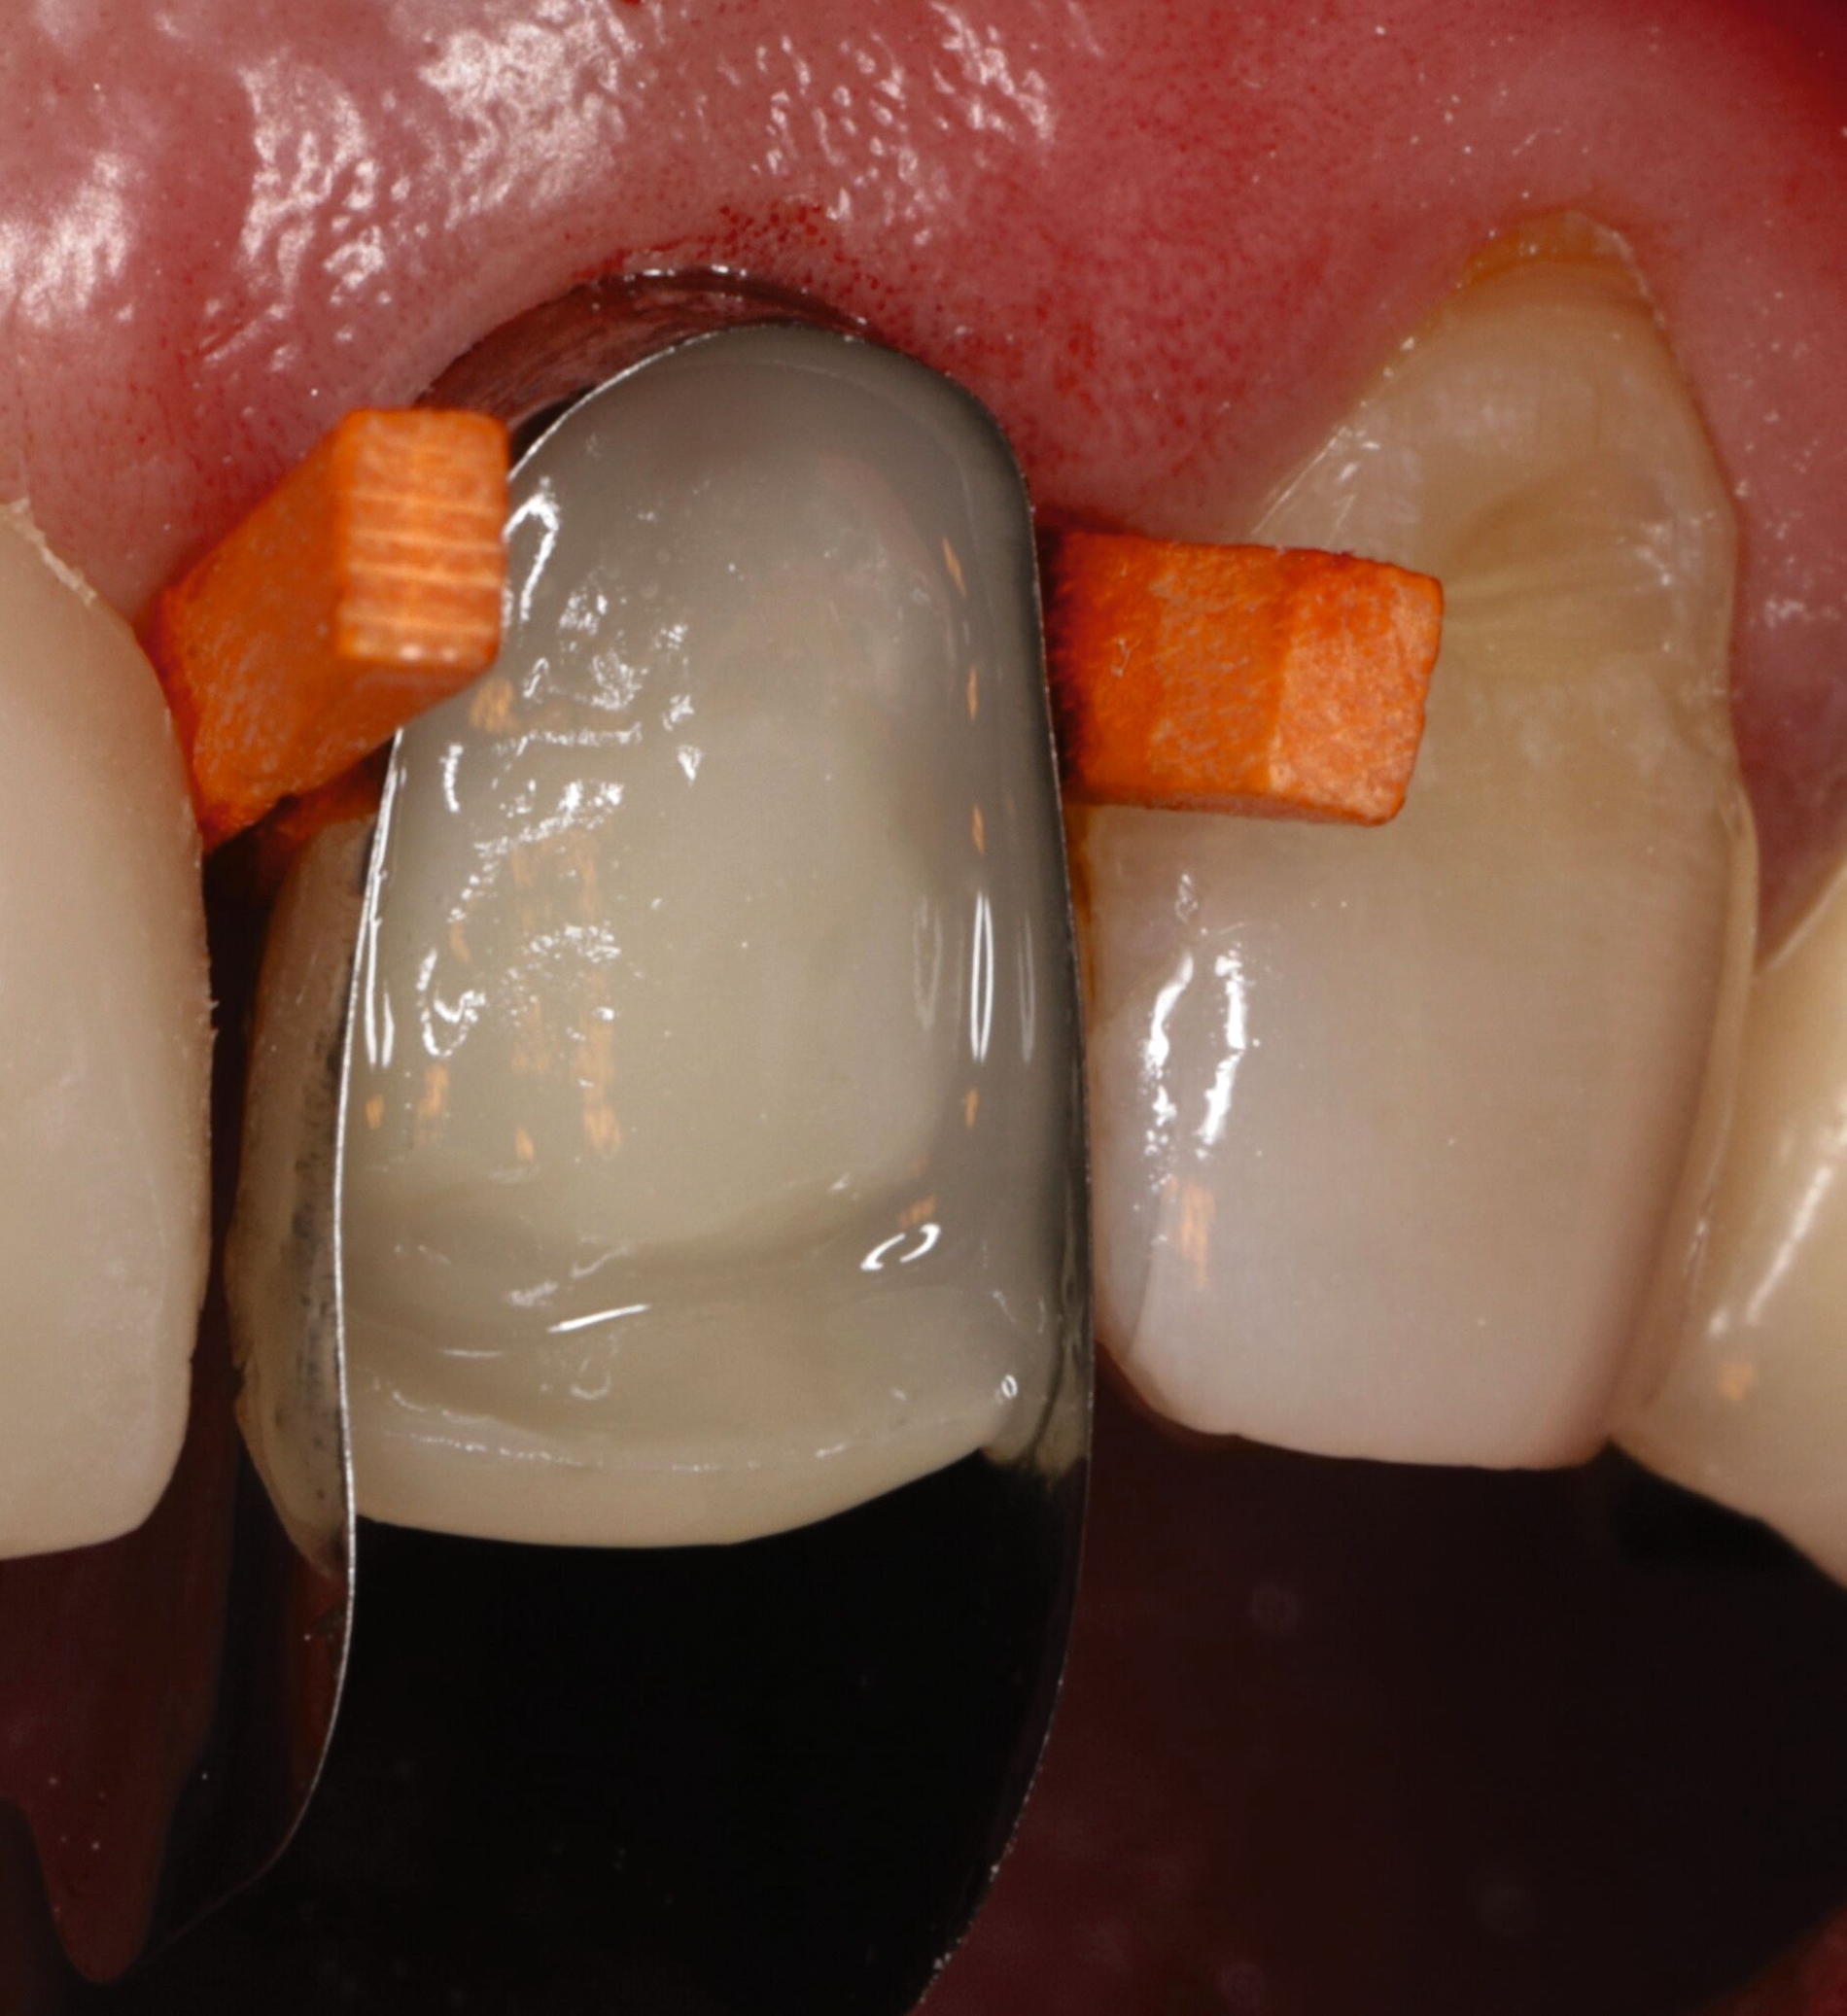

Die keilförmigen Defekte an den Zähnen 14 und 24 empfand der Patient bei Kontakt mit der Zunge als mechanische Irritationsstelle, weshalb eine Kompositreparatur zur Schonung der sonst intakten prothetischen Versorgung und der Zahnhartsubstanz eine sinnvolle und minimalinvasive Option darstellte [Jain et al., 2022]. Dabei wurden Retraktionsfäden zur Defektdarstellung eingebracht, die Dentinoberflächen mit einem Rosenbohrer mechanisch angeraut, die metallkeramischen Kronenränder mit CoJet-Sand silikatisiert, mit einem Silan silanisiert und die gesamte Restaurationsfläche mit einem 10-MDP-haltigen Universaladhäsiv vorbehandelt, um eine suffiziente Haftung zu generieren (Abbildungen 9 und 10) [Lührs, 2015; Stangel et al., 1987; Loguercio et al., 2015; Lührs et al., 2020; Ozcan und Niedermeier, 2002; Hickel et al., 2013]. Aufgrund der stark unterschiedlichen Transluzenz von Kronenmaterial und Komposit war es nicht möglich, eine unsichtbare Reparatur zu erzielen.